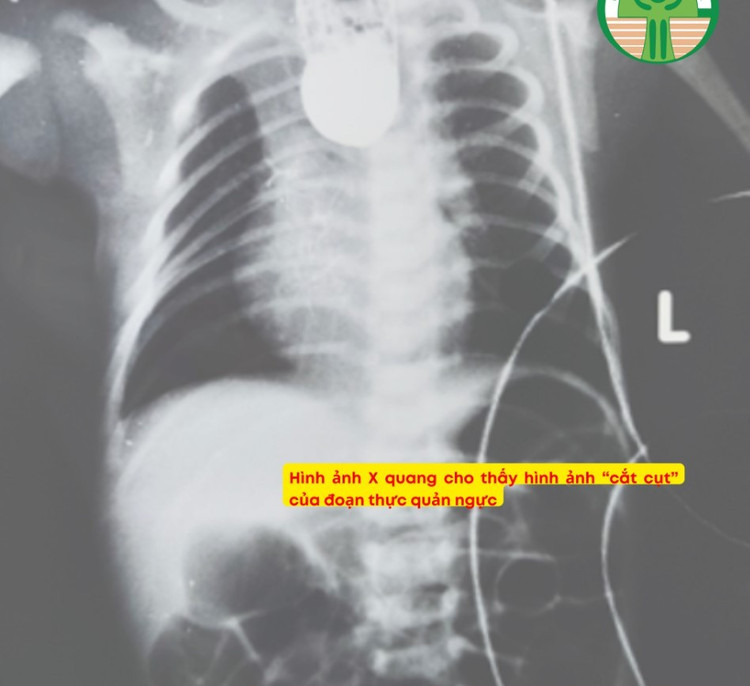

Bác sĩ Chiều cho biết, bệnh nhi là bé trai, sinh mổ ở 37 tuần tuổi thai, cân nặng lúc sinh 2,5 kg. Sau sinh, bé không thể bú sữa, xuất hiện tình trạng sùi bọt cua qua miệng, đặt thông dạ dày thấy vướng. Kết quả chụp X-quang cho thấy thực quản bị gián đoạn, với hình ảnh “cắt cụt” ở đoạn thực quản ngực.

thuc-quan.jpg

Ảnh BVCC